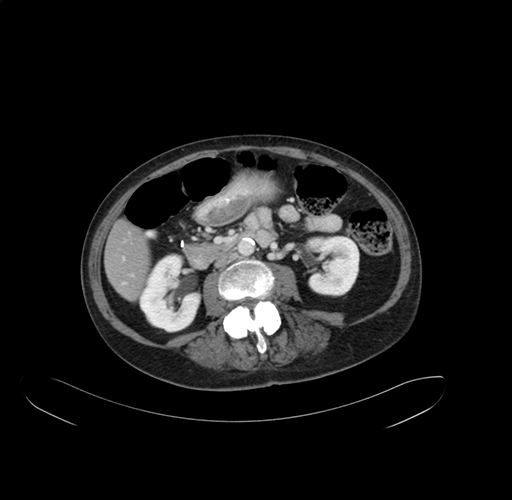

Axial Venous

Imaging analysis

Based on your CT findings, which issue(s) would give reason for "planned slowing down moment(s)" in this case?

Considering a standard right hepatectomy procedure, what step(s) of the operation would you do differently in this case?